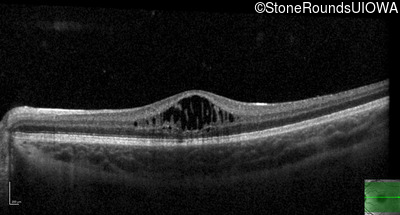

Optical Coherence Tomography - Left - 20/40 +2

Exemplar / OCT Stack